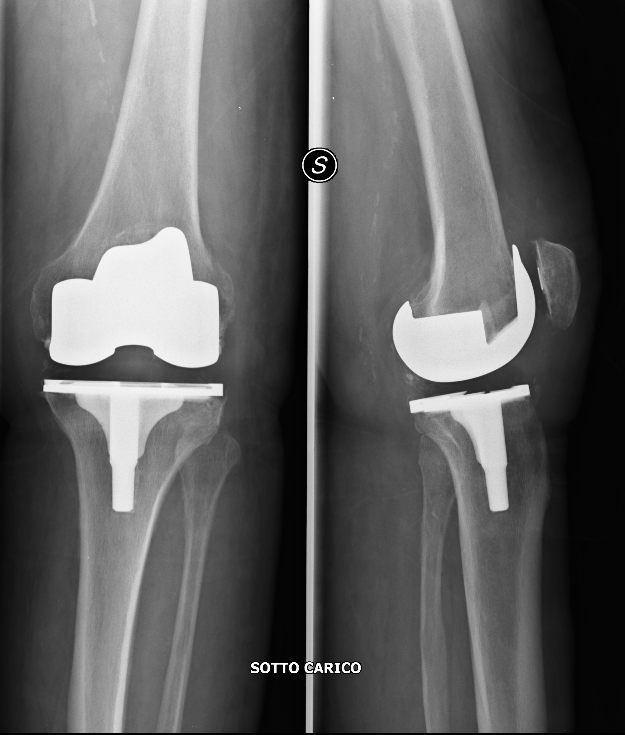

Artrosi del ginocchio o gonartrosi (protesi totale di ginocchio)